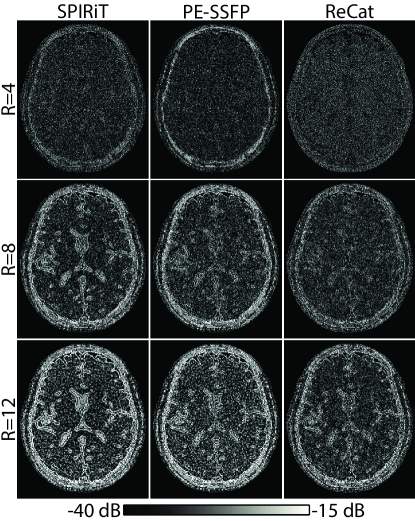

Following simulations, the potential of ReCat for accelerated in vivo bSSFP imaging was examined in the brain. Representative images from ZF, SPIRiT, PE-SSFP and ReCat are displayed for D=12 in Sup. Fig. S4, and for D=32 in Fig. 5. For D=12, ZF and SPIRiT suffer from relatively high levels of residual aliasing and noise interference compared to PE-SSFP and ReCat. While ReCat maintains the lowest reconstruction error, PE-SSFP and ReCat images are visually similar with detailed depiction of tissue structure even at high R. For D=32, ReCat again yields high-quality images, and in this case ReCat images appear sharper than PE-SSFP images. As opposed to PE-SSFP that jointly processes acquisitions, ReCat leverages additional information across coils. Thus, as D increases relative to N, performance improvements that ReCat provides over PE-SSFP might become more prominent.

Figure 4: SPIRiT, PE-SSFP and ReCat reconstructions of the simulated brain phantom were performed at N=4 and D=8. Error maps are shown for R=4, 8 and 12. ReCat outperforms SPIRiT and PE-SSFP for R>\textgreater4, and the level of error reduction increases towards higher R.

Figure 5: In vivo bSSFP acquisitions of the brain were performed for N=4, D=32. Representative reconstructions at R=8 are shown for ZF, SPIRiT, PE-SSFP and ReCat (top row). Error maps relative to fully-sampled acquisitions are displayed in logarithmic scale (bottom row; see colorbar). ReCat reduces reconstruction error and suppresses artifacts compared to other approaches, and achieves 34.1 dB PSNR; while SPIRiT and PE-SSFP yield to 33.7 dB and 32.4 dB, respectively. (See also Sup. Fig. S4.)